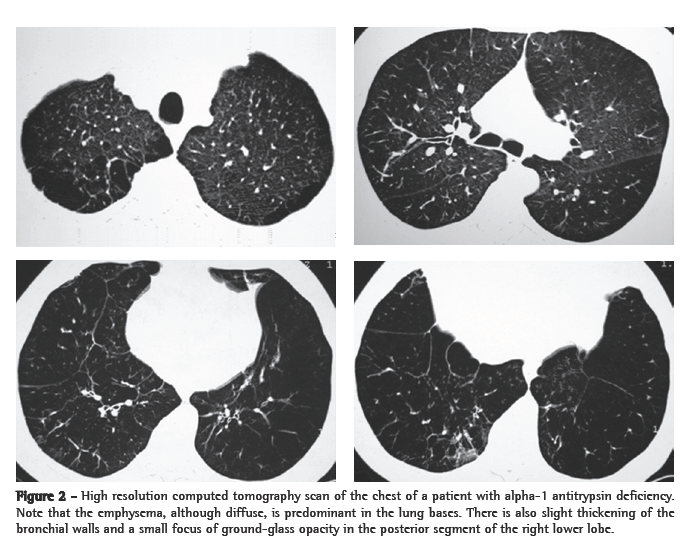

Chest X-rays revealed heterogeneous areas of consolidation, predominantly in the upper and middle lung fields, bilaterally, without signs of pleural effusion (Figure 1). The patient was admitted for investigation, and the HRCT scan requested revealed consolidations, peribronchial nodules and ground-glass opacities, with evident involvement of the upper and middle lung fields (Figure 2). There were no parenchymal cavitations, nor was there any pleural or mediastinal involvement.

Regarding the HRCT scan, the only study found in the literature reports that cardiogenic edema, as well as noncardiogenic edemas such as alveolar hemorrhage, can manifest as diffuse or ­multifocal pulmonary involvement, with ground-glass ­opacities, consolidations and smooth thickening of interlobular septa, with or without pleural effusion.(9) In our patient, alterations were located in the upper and middle lung fields, as is typically seen in inhalation-related lung diseases. Lesions are ­characterized by consolidations, peribronchial nodules and ground-glass opacities. Pulmonary alterations were extensive and had disappeared almost completely by the time of the control tomography scan, performed 15 days after drug use cessation and initiation of corticosteroid therapy.